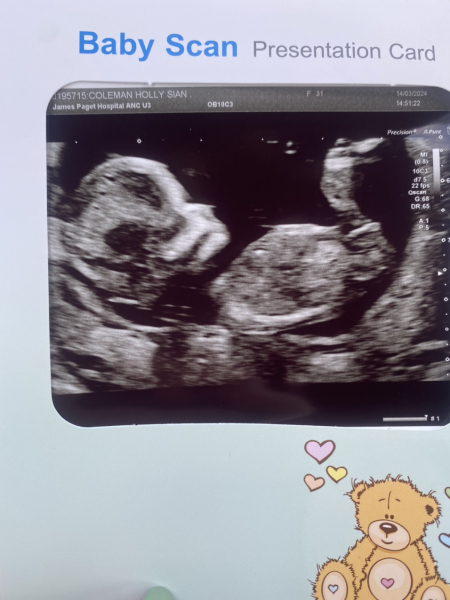

hol92 · 14/03/2024 16:52

Scan all went well feel so much happier and exited 😄 any guessed on girl or boy 🥰

@hol92 i think girl from the nub. I'm no pro though 🤣

What’s the gestation in this photo? Because anything after 12+5, I’m going with girl as the nub is parallel/pointing down 💕

@hol92 According to the theory, boy nubs point upwards/away from the spine from about 12+5 onwards which yours doesn’t.

Don’t swing for me if I’m wrong though 🤣 the nub on my 13 week scan photo is very girly, not a single boy guess, however gender is still unconfirmed meaning I can’t fully back the theory. I already have 2 boys so, we’ll see 😂